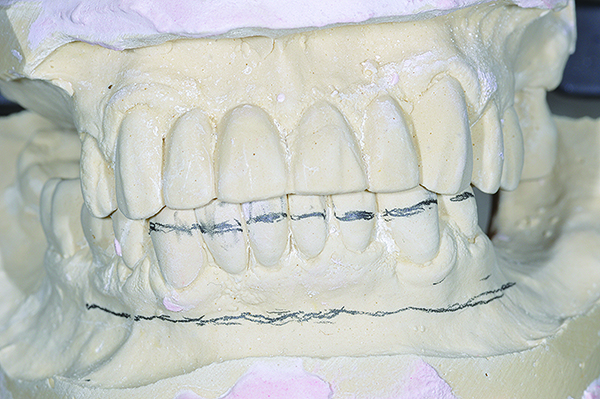

Bone reduction model surgery performed in mandibular arch to create 13 mm to 15 mm of inter-occlusal space required for the mandibular All-on-4 provisional restoration.

Figure 5